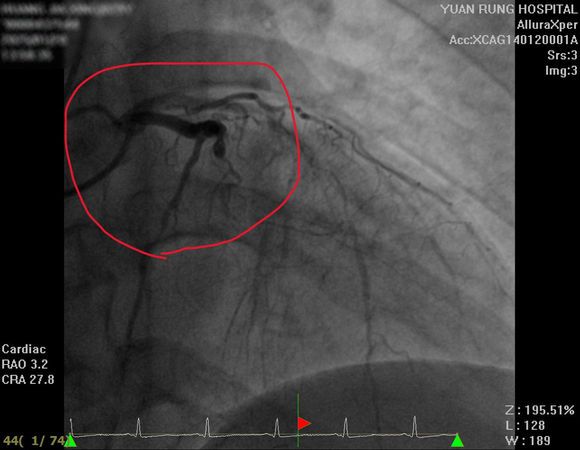

▲▼員榮醫院心臟內科陳裕峰主任解釋患者左前降支、左迴旋支及右冠狀動脈三條血管均嚴重阻塞。(圖/員榮醫院提供)

陳裕峰指出,一開始使用藥物治療,症狀有所改善,但心臟功能恢復仍不理想。進一步檢查顯示,患者左前降支、左迴旋支和右冠狀動脈3條血管均嚴重阻塞,這正是心臟功能下降的主因。

▲▼29歲患者因高血壓未服藥,加上生活作息不正常,心臟三根動脈血管都嚴重阻塞。(圖/員榮醫院提供)